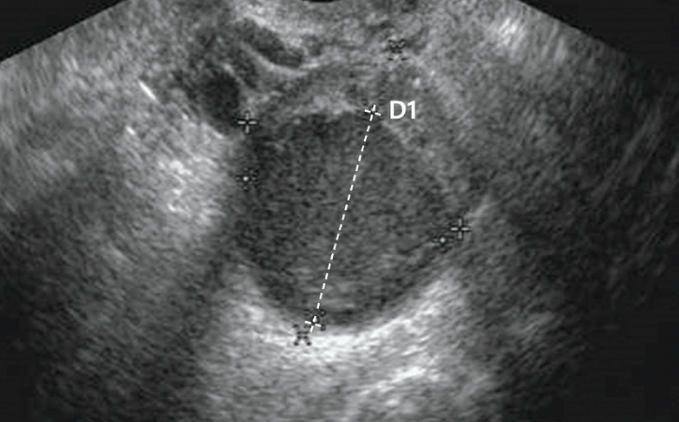

산과력 0-0-0-1인 31세 여성이 생리통으로 내원하였다. 2년 전 왼쪽 난소에서 5cm 크기의 낭종이 발견되어 난소낭종절제술 시행 후 6개월간 호르몬 치료를 받았다. 혈액검사 결과와 골반 초음파 사진이다. 치료는?

• 난소낭종절제술 과거력이 있으며 U/S상 homogenous hypoechoic ovarian cyst가 확인되므로 자궁내막종의 재발이 의심된다.